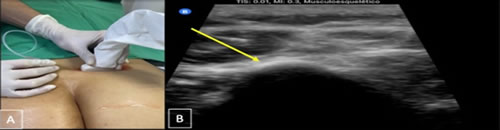

Se realizó un estudio de tipo observacional, retrospectivo, en pacientes diagnosticados con dolor lumbar crónico, signos y síntomas de atrapamiento de nervios cluneales o clunealgía llevados a bloqueo. Se revisaron las historias clínicas obteniendo información demográfica y clínica. Los criterios de inclusión son pacientes mayores de 18 años de edad con antecedente de patología lumbar por imágenes de resonancia o radiografía, con uno o más síntomas, dolor lumbar, irradiación a glúteo o miembro inferior, disestesia, exacerbación del dolor con cambios en la postura lumbar, y/o signos de clunealgía evidenciados en el examen físico de la historia clínica, a quienes se les realizó bloqueo analgésico de nervios cluneales (Figura 1 A y B) en el Hospital Universitario San José y Clínica Los Nogales en Bogotá durante el 1 de septiembre de 2019 al 31 de abril de 2021. Se excluyeron pacientes a quienes se les realizó otro tipo de procedimiento analgésico tipo bloqueos de bandas miofasciales y bloqueos facetarios con mejoría del dolor.

Fig. 1. A. Técnica de abordaje guiado por ultrasonido en los dos hospitales. Paciente en decúbito prono, transductor de alta frecuencia sobre el plano transversal de espina ilíaca posterior, la fascia toracolumbar y el borde lateral del músculo erector de la columna, al final del glúteo mayor se observa el glúteo medio conocido este punto como túnel graso. B: se realiza infiltración de medial a lateral al nivel de la espina ilíaca posterosuperior y sobre fascia toracolumbar, en el nervio cluneal superior (flecha amarilla) con solución analgésica con lidocaína al 1 % sin epinefrina 100 mg o bupivacaína al 0,25 % + betametasona 6 mg (volumen total 5 mililitros) a nivel perineural e interfascial. Observando la fascia toracolumbar y el músculo erector de espina separarse.